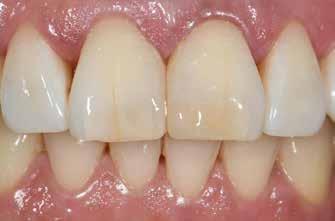

2-4. ábra: Gyakori problémák klasszikus megközelítéssel. 5. ábra: Tökéletes vészhelyzeti profil elülső szárnyas technikával. Dr. Jun Iwata, Japán jóvoltából.

2. eset: Egyszínű restauráció egy mikrodiasztémán, ahol a viasz nem kivitelezhető (1 óra ülésidő)